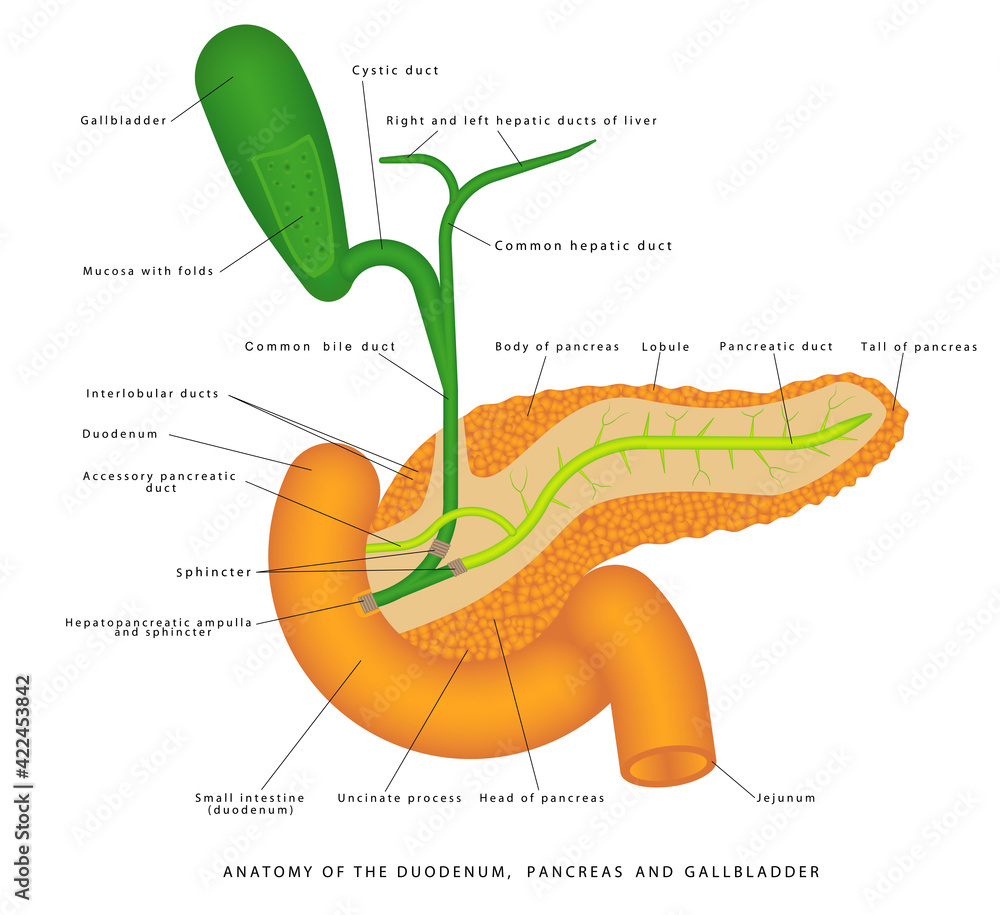

Bij een galwegontsteking (cholangitis) zijn de galwegen in of buiten de lever ontstoken. In de lever zitten veel kleine galkanaaltjes. Deze komen samen in de grotere galwegen. Via de grotere galwegen wordt de galvloeistof afgevoerd naar de galblaas en vervolgens naar de dunne darm. De galblaas.. Auszug. Die extra hepatischen Gallen wege in Form des Gallengangs und der Gallenblase garantieren den großen täglichen Bedarf an fettemulgierender Galle. Jede Unwegsamkeit darin provoziert ein Stenosemuster mit entsprechendem Gallenrückstau, der akut zum tödlichen Leberversagen und chronisch zu einem fibrodestruktiven Reaktionsmuster und.

De galblaas. Anatomie van de galblaas en galwegen. Anatomie van de twaalfvingerige darm en de

Anatomy of the gallbladder and bile ducts Surgery Oxford International Edition

Lever (Hepar)Galwegen en Galblaas